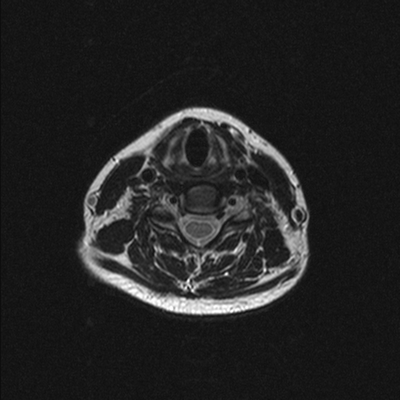

На сериях МРТ, выполненных в аксиальной, корональной и сагиттальной плоскостях, взвешенных по Т2-ВИ, Т1-ВИ и STIR-ИП, получены изображения шейного отдела позвоночника.

Определяется патологический кифоз с вершиной на уровне тел позвонков С5-С6.

Выявляются дегенеративно-дистрофические изменения в виде умеренно выраженного понижения интенсивности сигнала от межпозвонковых дисков в сегментах С2-Th1, со снижением высоты в сегментах С5-С7, а также формирования передних и заднебоковых краевых костных разрастаний. Унковертебральный артроз на уровне сегментов С5-С7.

В смежных отделах позвонков С6-С7 определяются зоны гиперинтенсивного МР-сигнала на Т2-ВИ, STIR-ИП и гипоинтенсивного в Т1-ВИ (вероятно, обусловленные отёком вещества костного мозга).

Определяются неровности смежных замыкательных пластин тел позвонков С5-С7 за счет хрящевых узлов Шморля.

В сегменте С3-С4 под краевыми остеофитами определяется дорзальная медианная протрузия межпозвонкового диска, размером до 2,5мм. Переднее субарахноидальное пространство деформировано. Межпозвонковые отверстия умеренно сужены, достоверных данных за компрессию корешков нервов не выявлено. Передне-задний размер позвоночного канала до 14мм.

В сегменте С5-С6 под краевыми остеофитами определяется задняя диффузная протрузия межпозвонкового диска, размером до 2,5мм. Переднее субарахноидальное пространство деформировано. Межпозвонковые отверстия умеренно сужены, достоверных данных за компрессию корешков нервов не выявлено. Передне-задний размер позвоночного канала до 13мм.

В сегменте С6-С7 под краевыми остеофитами определяется задняя диффузная протрузия межпозвонкового диска, размером до 2мм. Переднее субарахноидальное пространство деформировано. Межпозвонковые отверстия умеренно сужены, достоверных данных за компрессию корешков нервов не выявлено. Передне-задний размер позвоночного канала до 14мм.

Сигнальные характеристики от шейных позвонков не изменены.

Видимые отделы спинного мозга в размерах не увеличены, имеют четкие контуры и однородную структуру, интенсивность МР сигнала не изменена.

Паравертебральные мягкие ткани не изменены.

МР-признаки дегенеративно-дистрофических изменений шейного отдела позвоночника с нарушением статики. Протрузии дисков на уровне сегментов С3-С4, С5-С6, С6-С7. Унковертебральный артроз. Хрящевые узлы Шморля смежных замыкательных пластин тел позвонков С5-С7.